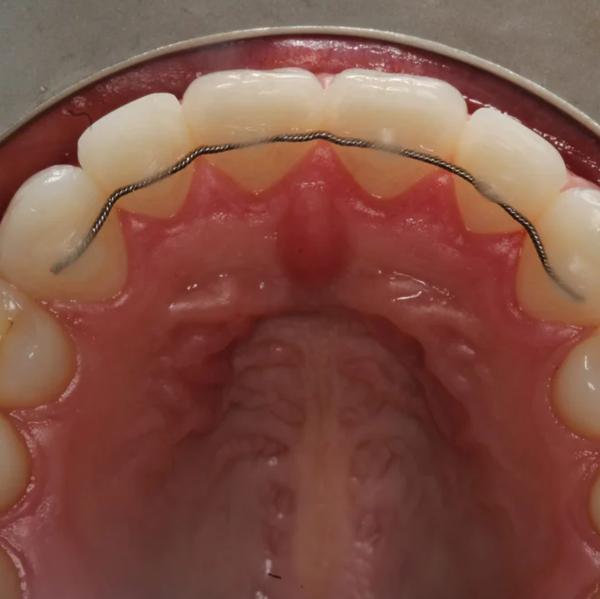

Image Gallery

Pictures That Speak